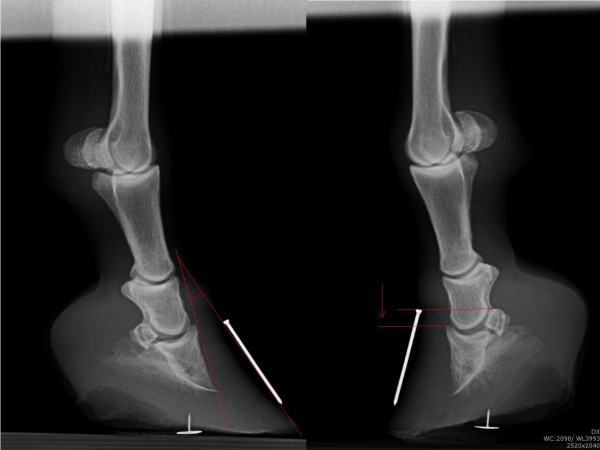

Chronicky schvácené kopyto